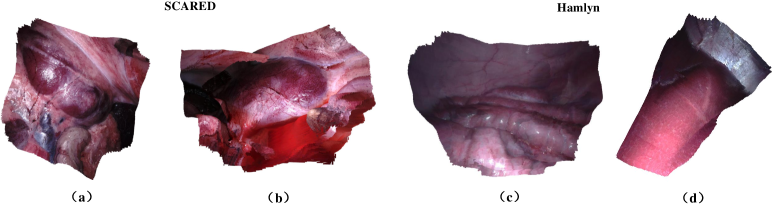

Hamlyn444http://hamlyn.doc.ic.ac.uk/vision/ involves phantom heart model videos with the point cloud ground truth and in vivo endoscopic videos taken from various surgical procedures.

For depth estimation, we perform extensive experiments on the SCARED dataset and then apply models trained on the SCARED to the SERV-CT dataset and Hamlyn dataset to validate the generalization ability. In addition, we show some qualitative depth results on the EndoSLAM dataset in Fig. 7. We refer to the Eigen-Zhou evaluation protocol [16, 68] established on the KITTI benchmark and split the SCARED dataset into 15351, 1705, and 551 frames for the training, validation and test sets, respectively. We conduct ego-motion estimation on the SCARED dataset and the EndoSLAM dataset. We select two consecutive trajectories of 410 and 833 frames to evaluate performance on the SCARED dataset. In terms of the EndoSLAM dataset, we conduct 5-fold cross validation on the challenging LowCam of the ex vivo part, and each of the 5 models is tested on trajectories from one organ and trained on the rest. Besides, we demonstrate quantitative point cloud results and qualitative surface reconstructions on the SCARED dataset and Hamlyn dataset in Table 12, Table 13 and Fig. 9.

We directly validate the models trained by the SCARED on the SERV-CT and Hamlyn datasets without any fine-tuning. We only adjust the resolution of test frames to 320×256320256320\times 256 pixels and feed them to DepthNet. As presented in Table 4 and Table 5, our framework achieves superior results than the other methods, revealing its strong generalization ability across different patients and cameras. A qualitative comparison can be seen in Fig. 7.

4.7 SCARED and Hamlyn Point Cloud